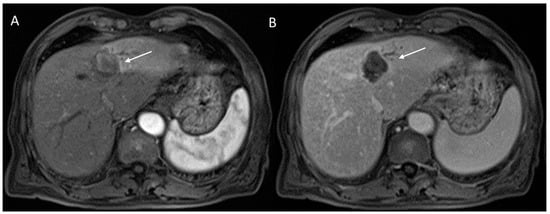

2.2.3. HCC Diagnosis

2.2.4. Ancillary Features